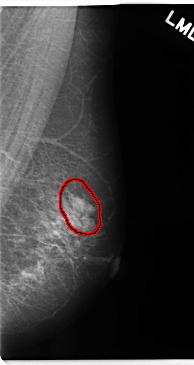

FILE: C_0186_1.LEFT_MLO.OVERLAY

TOTAL_ABNORMALITIES 1

ABNORMALITY 1

LESION_TYPE MASS SHAPE OVAL MARGINS CIRCUMSCRIBED

ASSESSMENT 4

SUBTLETY 5

PATHOLOGY BENIGN

TOTAL_OUTLINES 1

BOUNDARY